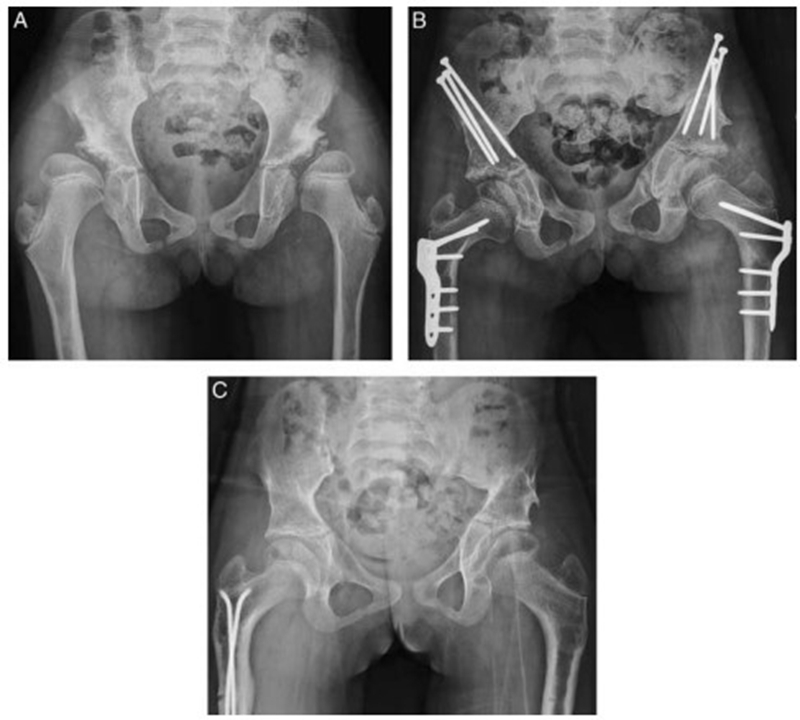

7岁儿童,股骨头缺血坏死,经JST微创骨盆三联截骨后,末次随访提示股骨头形态恢复满意,头臼关系适应好